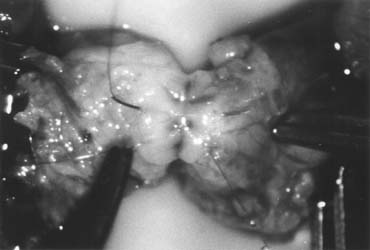

Bilateral 1-cm transverse scrotal incisions provide good exposure with a minimum of scrotal skin bleeding (Fig. 1). Alternatively, a single vertical incision in the median raphe may be employed. Use of loupes or an operating microscope allows ready identification of a relatively avascular area on the tunica albuginia where an incision may be made. A 3- to 4-mm incision is made in the tunica albuginea with a 15-degree microknife (Fig. 2). A pea-size sample of seminiferous tubules is excised with razor-sharp iris scissors (Fig. 3). When handling testis biopsy material for permanent fixation, it is important to avoid tissue traumatization by forcep handling in any way as this may distort the testicular architecture.

Fig. 2. A 3- to 4-mm incision is made on the tunica albuginia, avoiding major crossing vessels.

Fig. 3. Sampling of seminiferous tubules using razor-sharp iris scissors.